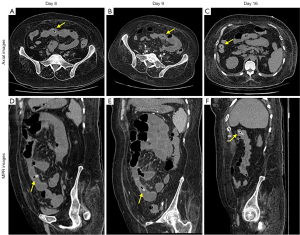

All cases in the reference reported group were inpatients. Among them, 21 (91.30%) patients showed signs of inflammation with elevated white blood cell count, procalcitonin, and C-reactive protein. In the present study group, the laboratory findings of many outpatients were not traceable. The patients in the present study group received both outpatient and inpatient treatment, including surgery (Figure 3), endoscopy (Figure 4), conservative treatment, or non-intervention with follow-up (Figure 5). For the inpatients in both groups, surgical removal is the most common treatment.

Roles of CT in detecting and tracing subphrenic jujube pits

In both groups, all jujube pits could be detected by CT. Except details of CT detection in 24 patients were not available (Table 2), the detection rate on the initial imaging reports were different in two groups (present study n=24, 96%; reference report group n=14, 66.67%). Jujube pits could be found anywhere along the gastrointestinal tract, small intestine is the most common site (n=35, 50.00%). There were no statistically significant differences between the location distributions of the two groups. Size details of most patients were lack in reference report group. In present group, larger jujube pits (≥2.5 cm) were either lodged in or perforated the gastrointestinal tract without exception on CT images. Patients who did not undergo surgery or endoscopy to remove the jujube pits needed CT scans to monitor them until they were passed with stool (Figure 5).

The sensitivity of CT in detecting subphrenic jujube pits was 100% on retrospective reviews of CT images. However, a lower diagnostic sensitivity (66.7% in reference group and 96% in our group) is owing to radiologists’ insufficient cognition of foreign bodies (35). According to our experience, when the long axis of the jujube pit is perpendicular to the axial plane, it appears as a small ring hence jujube pits can be easily missed or mistaken for intestinal gas content for physicians or junior radiologists. Senior radiologist can be alarmed by incidental signs of fat stranding and thickening of gastrointestinal wall. With the help of multiplanar reformation, shape of jujube pit and the relationship between sharp points and the digestive tract wall are better visualized (Figures 3-5), eventually the jujube pit was detected and more information can be provided for clinical management (16). Max-HU of jujube pit ROI in this study was lower than or equal to 329 HU, which can act as a threshold value to help differentiate jujube pits from other high-attenuation materials such as metal foreign bodies.